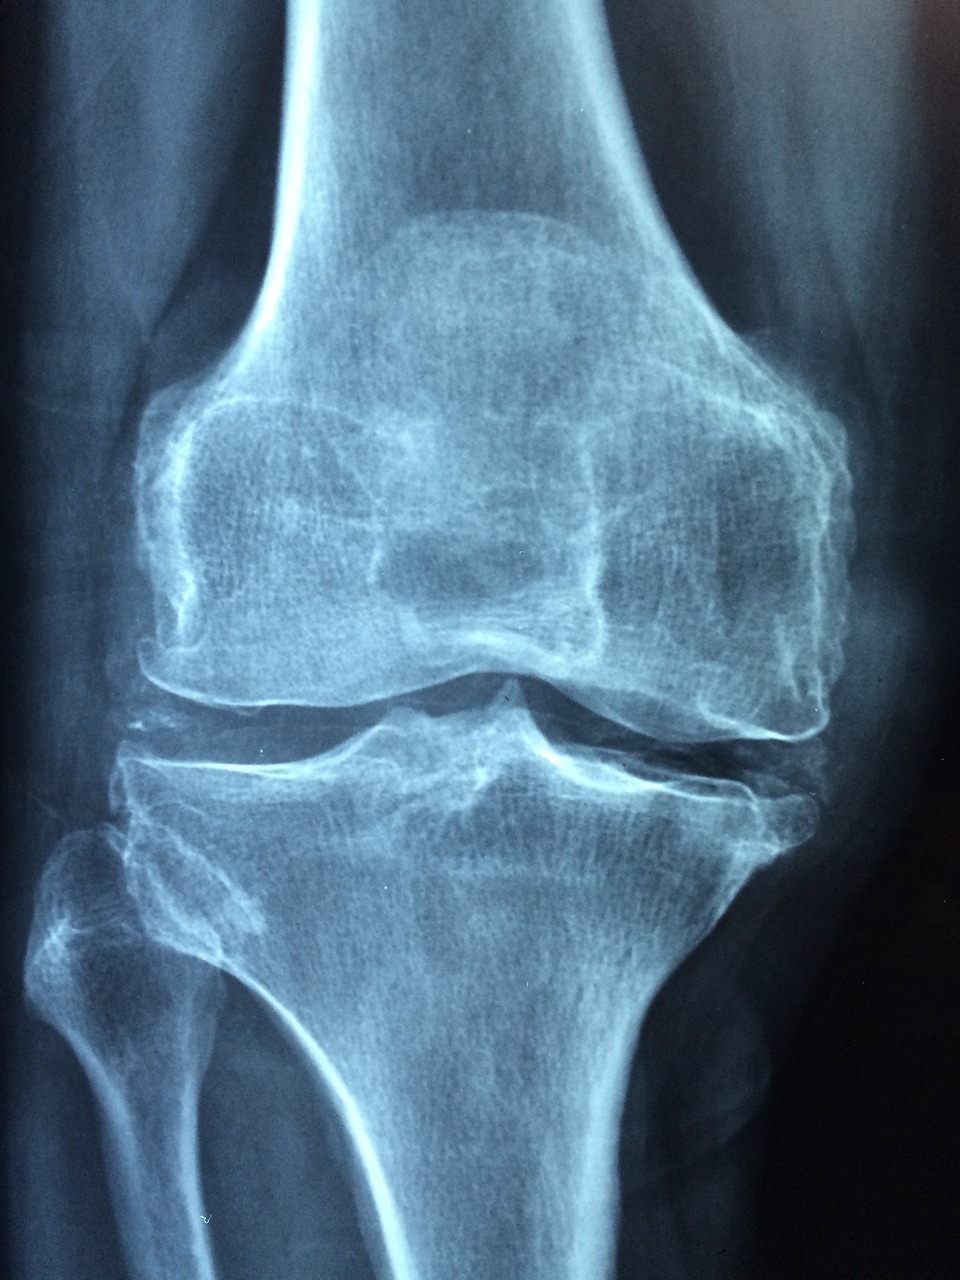

2️⃣ 염증과 단순 통증을 구분하는 5가지 핵심 신호

✅ 무릎 인공관절 수술 후 통증이 단순 회복 과정인지, 아니면 염증으로 인한 이상 반응인지를 알아보는 건 매우 중요합니다.

다음과 같은 5가지 신호가 나타난다면 단순 통증이 아닐 수 있습니다.

● 1. 통증이 점점 심해진다

초반보다 나아지지 않고, 오히려 더 아파지는 경우는 염증을 의심해야 합니다.

특히 밤에 아파서 잠을 설칠 정도라면 주의가 필요하죠.

● 2. 수술 부위가 갑자기 붉게 변하거나 열이 난다

보통의 부기는 2~3주차에 감소하는데, 이 시기 이후에 다시 붉어지거나 열감이 심해지면

무릎 인공관절 수술 후 염증의 주요 증상 중 하나입니다.

● 3. 진물이나 고름 같은 분비물이 나온다

수술 부위에서 맑지 않은 액체가 나온다면 염증 가능성이 매우 높습니다.

특히 냄새가 나거나 누런 고름이 나오는 경우는 감염까지 의심해봐야 합니다.

● 4. 움직임이 갈수록 힘들고 무겁게 느껴진다

관절이 뻣뻣해지고 통증 때문에 움직임이 줄어들면, 내부 조직의 염증 반응일 수 있습니다.

● 5. 몸 전체에 미열이 있거나 오한, 피로감이 동반된다

국소 염증이 전신으로 번질 경우, 열이 나거나 컨디션이 급격히 나빠질 수 있습니다.

이럴 땐 반드시 병원 진료를 받아야 합니다.

💡 이런 증상이 2가지 이상 동시에 나타난다면 빠른 시간 내 정형외과 전문의를 방문하셔야 합니다.